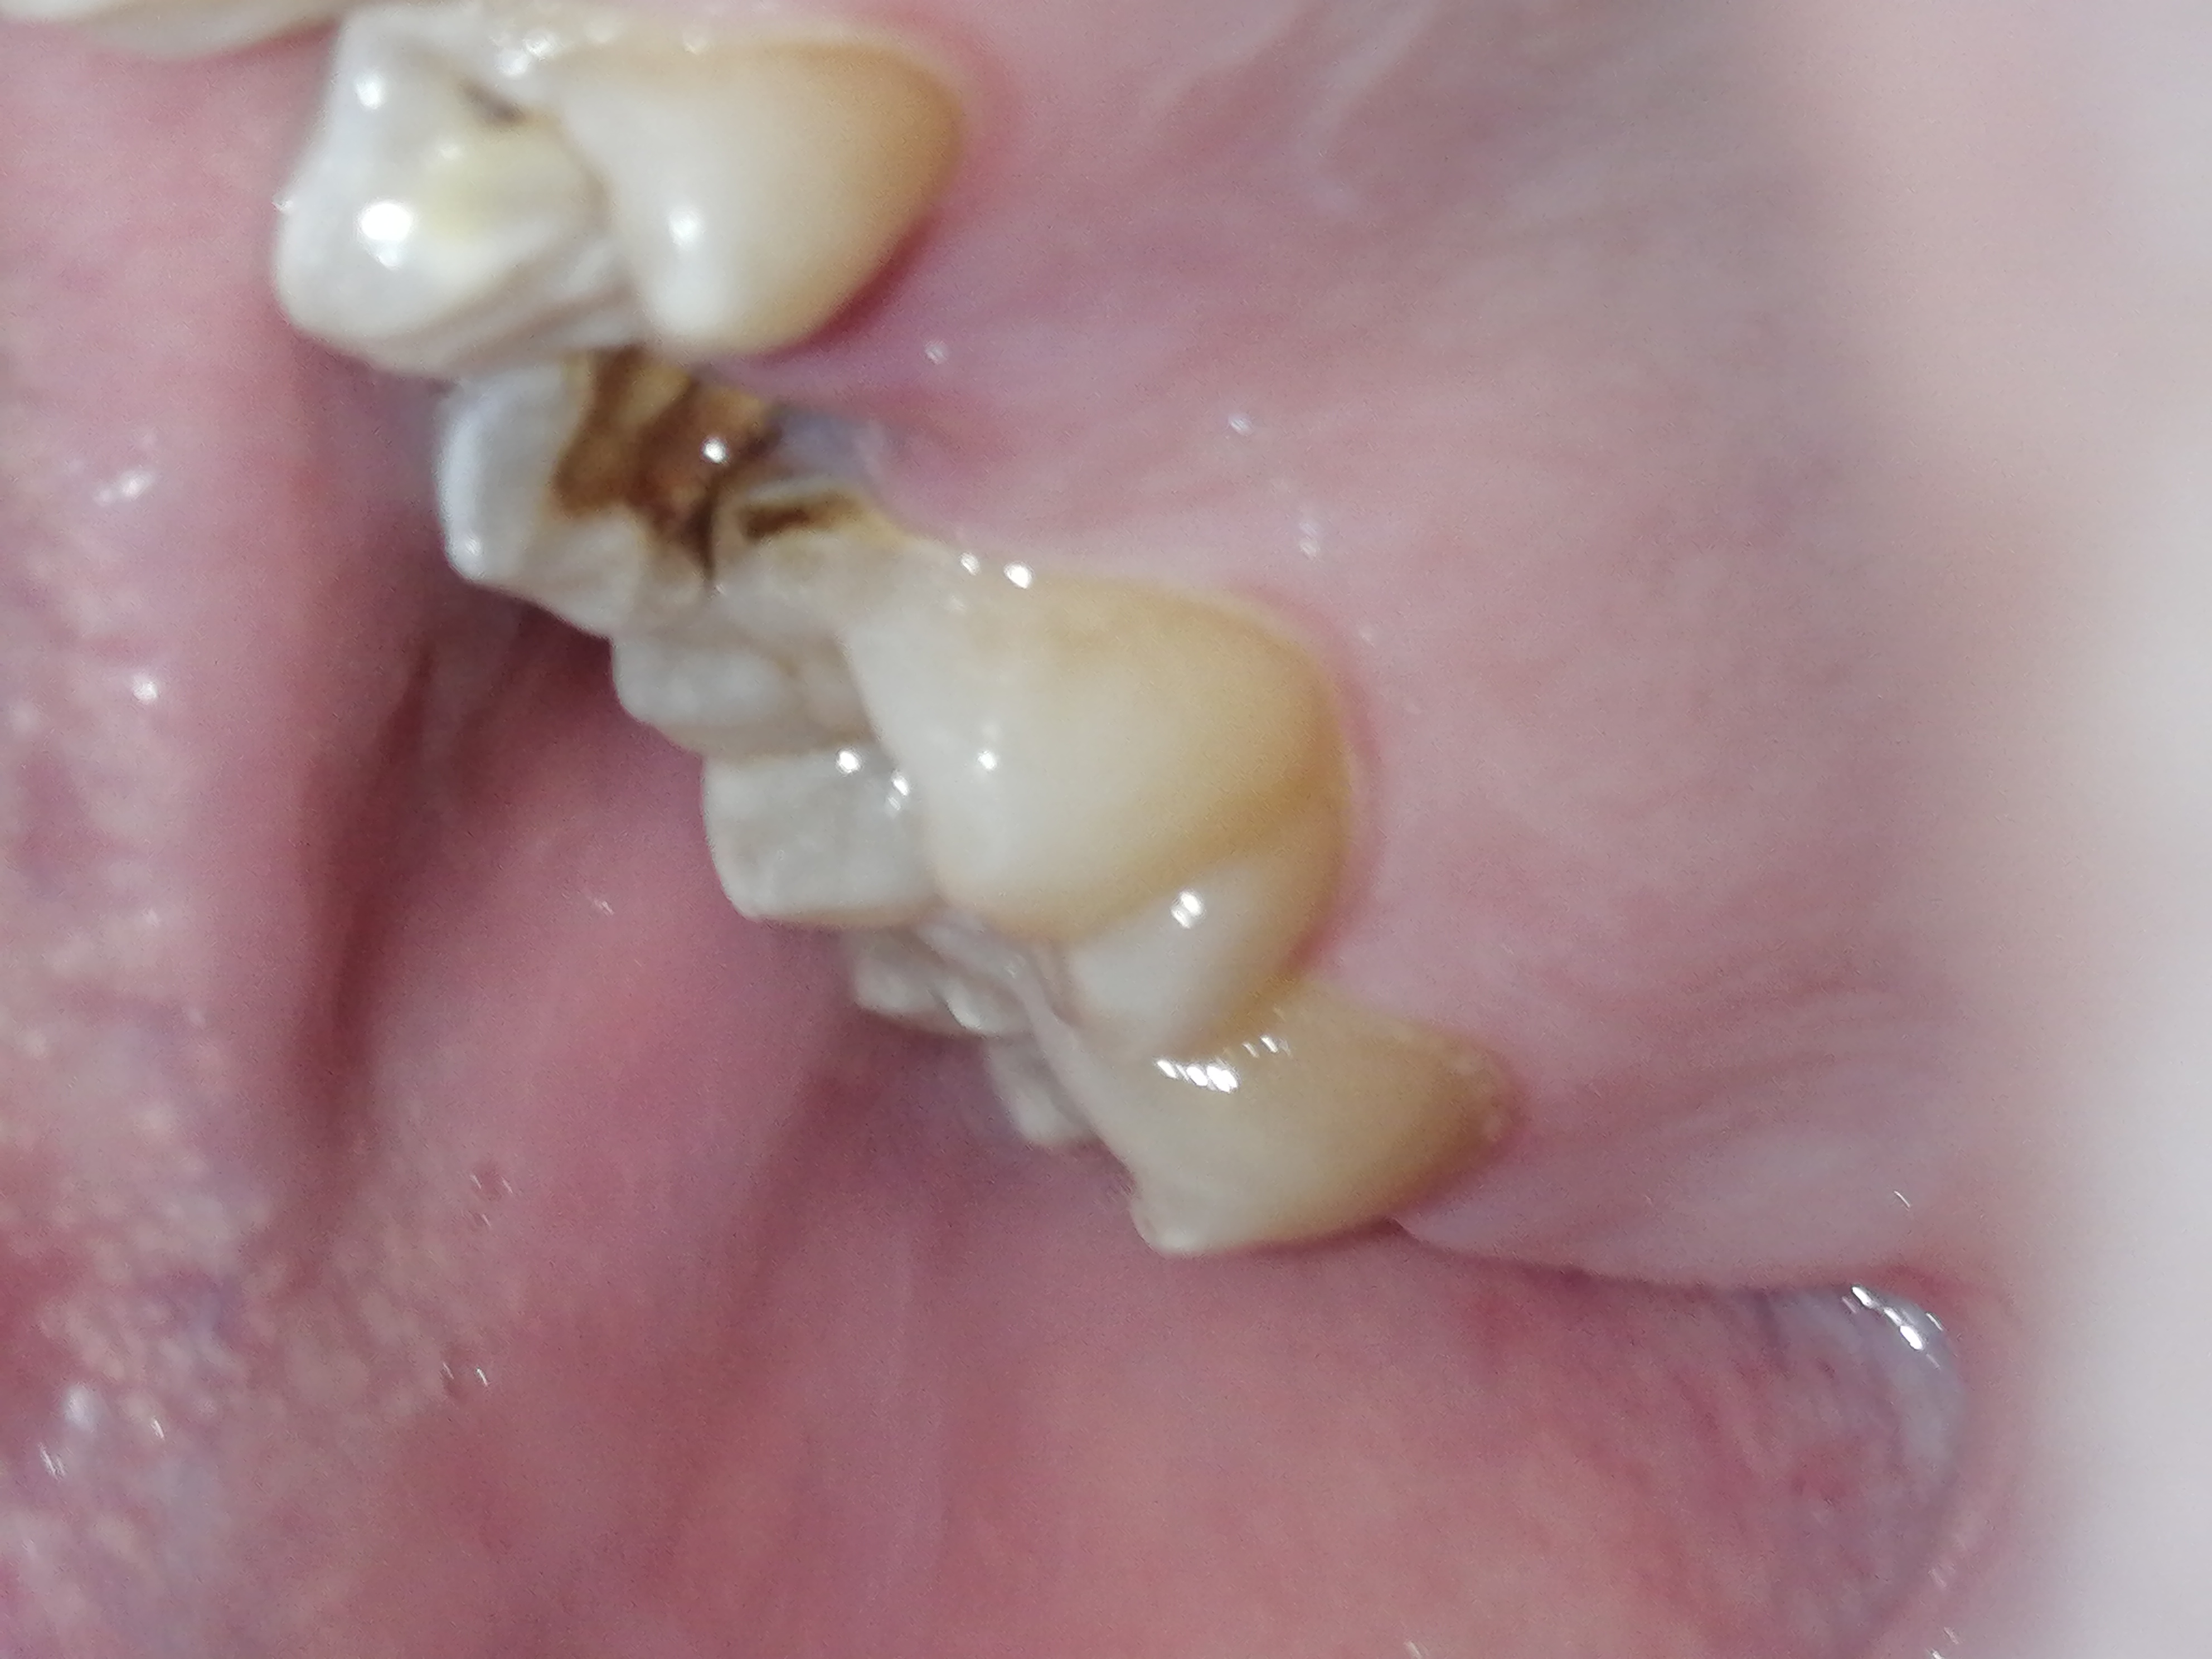

Аноним 10/08/25 Вск 18:26:58 1635518 35

1000070960.jpg 313Кб, 1117x832

1117x832

1000070961.jpg 180Кб, 882x704

882x704